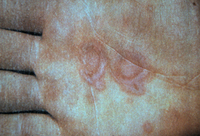

Palmar target lesions in erythema multiforme

From the personal collection of Nanette Silverberg, MD, FAAD, FAAP